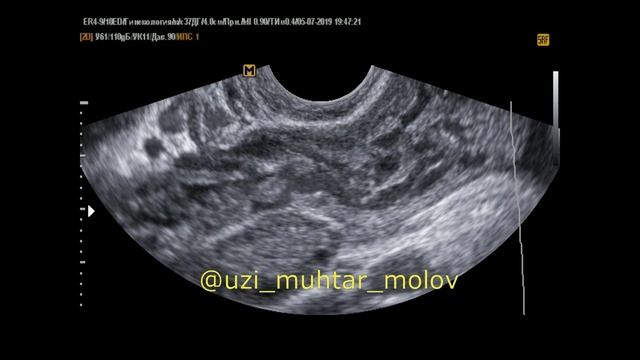

Видео Тромбоз Вен малого таза ОМТ УЗИ обучение @dr.molov Опубликовано 26.07.2025 в 00:00:00 Продолжительность: 00:02:08 1 . Видео Тромбоз Вен ОМТ, видео от 2025-07-26 загрузил на rutube УЗИ обучение @dr.molov...